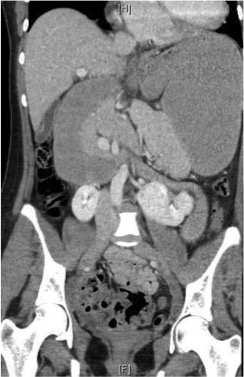

After initial resuscitation with an intravenous (IV) bolus of normal saline, the patient was kept nil orally with maintenance IV fluids (0.45% sodium chloride with 5% dextrose). Abdominal radiographs revealed marked gastric distension with small bowel ileus, indicating possible gastric outlet obstruction or gastric volvulus (Figures 2 and 3). Contrast-enhanced computed tomography (CT) scans of her abdomen and pelvis showed severe dilatation of the stomach and the first and second parts of the duodenum and a collapsed distal small bowel (Figures 4 and 5). These findings were consistent with small bowel obstruction at the level of the mid or distal duodenum, possibly due to volvulus or superior mesenteric artery syndrome (SMAS). The radiographs also confirmed lumbar dextroscoliosis and severe pectus excavatum. The decision was made to perform an urgent laparotomy to relieve her intestinal obstruction.

Figure 4. CT of the abdomen and pelvis, coronal view; arrows show severe dilatation of the stomach and the first and second parts of the duodenum, along with a collapsed distal small bowel.